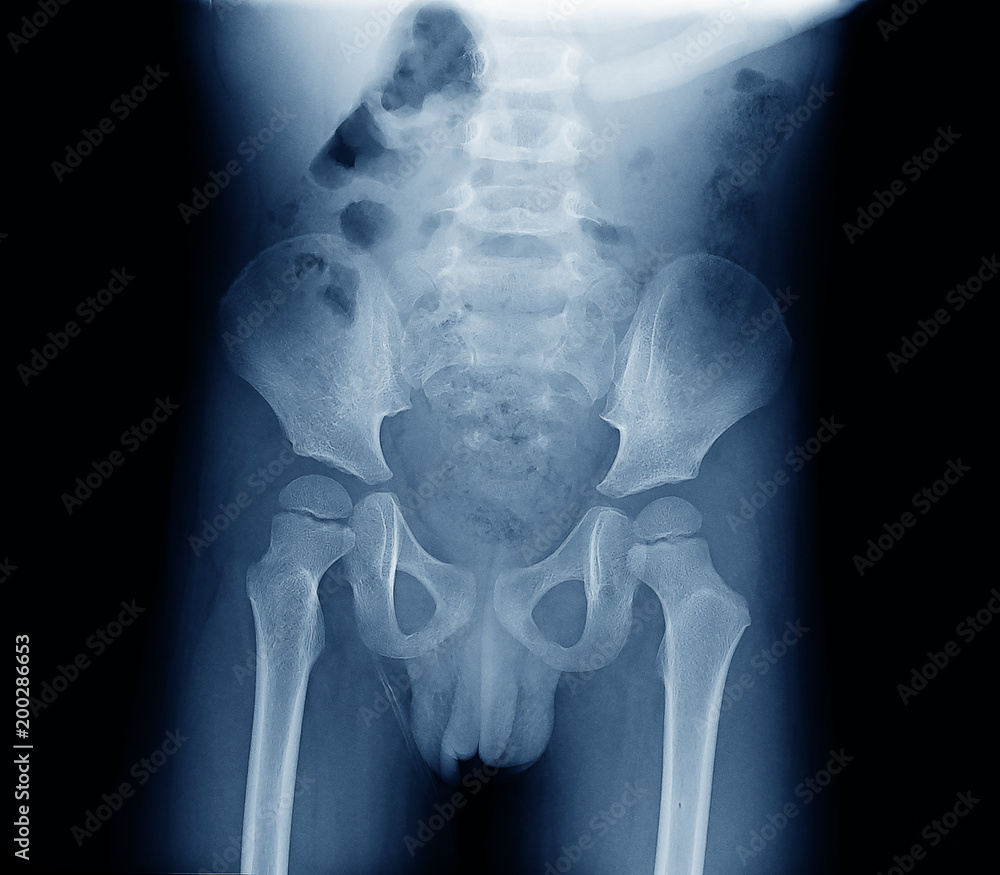

The main pathology is congenital dislocation of. A hip X-ray is a safe and painless test that uses a small amount of radiation to make images of the hip joints where the legs attach to the pelvis. The doctor hears or feels a hip click when moving the infants thigh outward during a routine.

This is necessary to make the diagnosis or to be sure the hip is normal. For a simple baby hand xray the child can usually be scanned using a standard device using just a light. An X-ray of the pelvis focuses specifically on the area between your hips that holds many of your.

X Ray Image Of Child Bone Show Pelvis Hip Joint Spine Stock Photo Adobe Stock